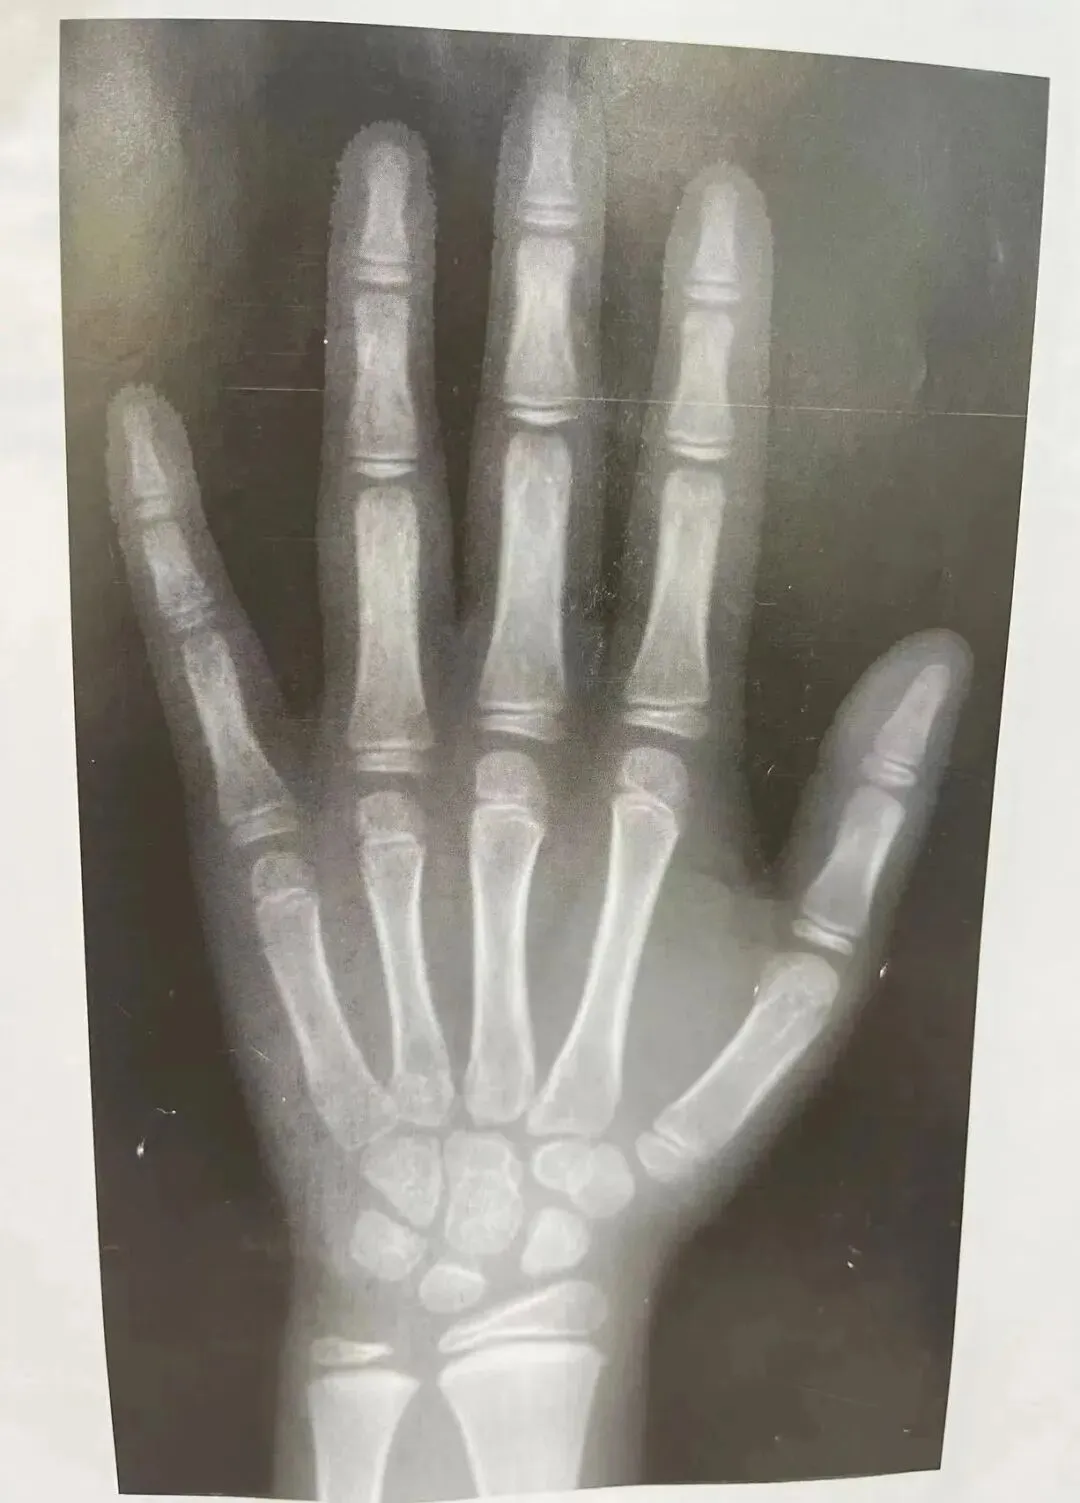

检测设备先进精准:引进国际标准化骨龄分析系统,通过拍摄孩子左手腕部 X 光片,运用先进算法精准分析骨龄,可清晰呈现孩子骨骼发育程度,误差极小。